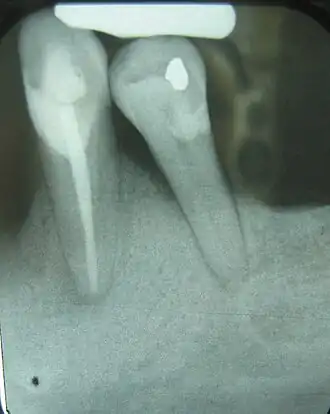

Crown-to-root-ratio is the ratio of the length of the part of a tooth that appears above the alveolar bone versus what lies below it.[1] It is an important consideration in the diagnosis, treatment planning and restoration of teeth, one that hopefully guides the plan of treatment to the proper end result.

These terms can also be used to refer to the clinical sense of the words, as relative crown and relative root, by describing how much tooth remains surrounded by bone. As the inflammation associated with periodontal disease causes the bone to resorb and disappear, revealing more of the root structure, the effective crown height in relation to the effective root height is reduced and the prognosis shifts from favorable to unfavorable.

Clinically, the anatomical definitions don't really matter; what is important in terms of support for the teeth within the bone is how much of the teeth remain embedded; this is where the crown-to-root ratio becomes important.

The natural crown-to-root ratio is thus termed a favorable crown-to-root ratio, because the root system existing within the surrounding bone is more than sufficient to support the tooth under normal physiologic stresses. After some bone loss is incurred, though, and more root structure is visible outside of the supporting bone, not only is there less effective root support, but there is an increased height of revealed tooth structure that this now diminished submerged root is responsible for supporting. In a way, then, each millimeter of lost bone contributes, for example, to a millimeter of less support and a millimeter of more structure to support. As can be extrapolated, this can easily become a very serious problem once three, four or five millimeters of bone have been lost due to periodontal disease.[3] The minimum crown-to-root ratio necessary is 1:1; any less support provided by the roots drastically reduces the prognosis of the tooth and its restoration.